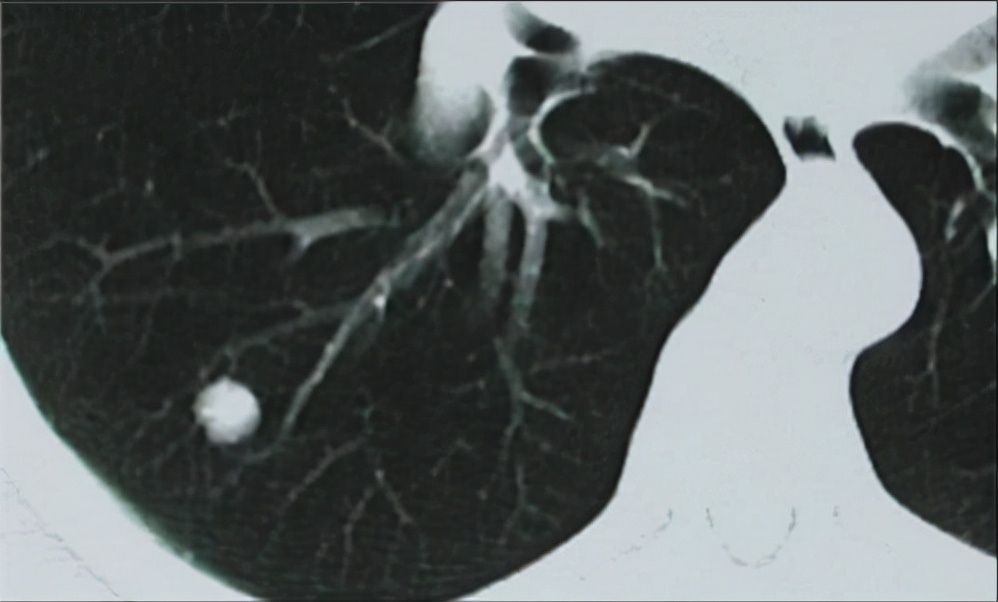

什么是肺小结节?在开始谈肺小结节之前,有必要搞清楚它的定义。肺小结节是胸部X线影像学的一个描述性语言,通常是指肺内单个、圆形、不透明、边界清楚的且直径小于2cm的结节。临床上,通常把肺实质内大于3cm的病灶称为肺部肿块,而按不同的直径,把小于3cm的病灶称为肺结节;小于2cm的结节称之为肺小结节;小于5mm的结节称为肺微小结节。

近年来,体检查出肺上有小结节的人渐渐多了起来。曾有媒体称每四人体检低剂量螺旋CT,就有一人被查出肺小结节。虽然这一数据的真实性有待考证,但其检出率越来越高是不争的事实。这其实和CT技术的日新月异大有关系——多层螺旋CT已能洞悉和分辨直径2至3毫米的结节。

随着经济的发展和低剂量螺旋CT在体检中的广泛运用,肺小结节的检出率越来越高。各种文献报道的数据也各不一样,平均为24-40%。国外有研究发现,低剂量螺旋CT筛查,正常人群肺结节检出率为24%,也就是4个人就有至少有一个人能查出肺结节。而有些一些研究甚至更高,可高达40%。国内有研究报告《中国医学影像技术2003年07期 》发现: 如果降低螺距,分别采用螺距 1,1.5 ,2进行扫描。由三名医师在不知模型结节的情况下分别读片。结果发现肺内微结节和小结节的检出率分别为 100% ,89.6% 。